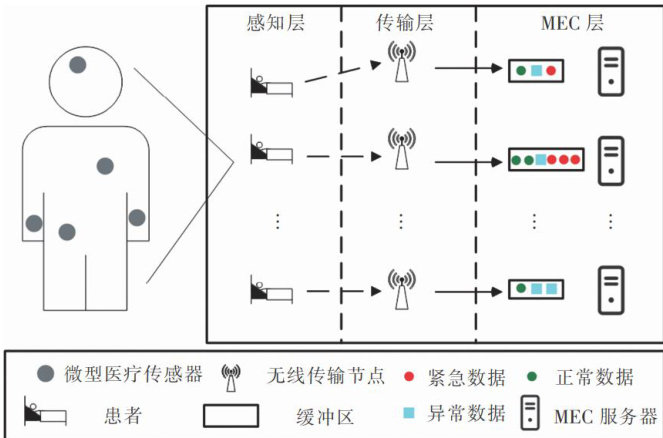

信息安全技术 | 多网关无线医疗传感器网络中基于PUF的轻量级匿名认证协议

信息安全技术 | 多网关无线医疗传感器网络中基于PUF的轻量级匿名认证协议